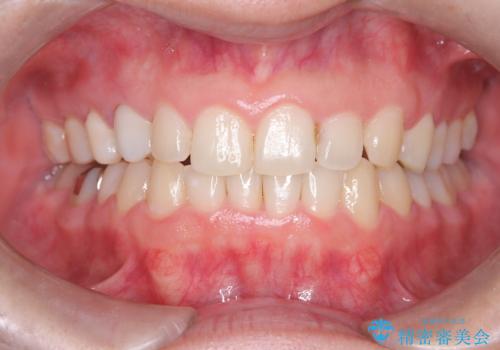

前歯の突出を防ぎながらガタつきを解消。上下左右4番抜歯による審美ワイヤー矯正

担当医 河口智英